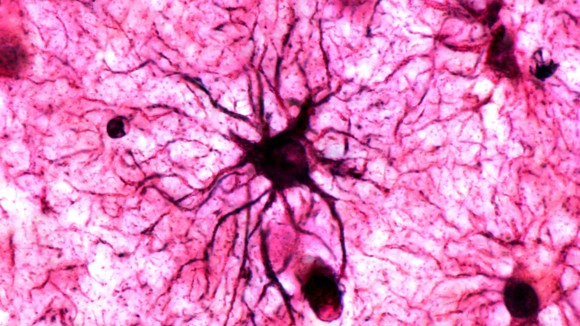

Courtesy of NatureMagazine

Wako, Jepang - Kenangan tentang peristiwa emosional seringkali lebih mudah diingat dibanding kenangan biasa. Sebuah studi terbaru mengungkap bahwa sel otak bernama astrocytes berperan penting dalam menstabilkan ingatan jangka panjang tersebut.

Sebelumnya, astrocytes dianggap hanya sebagai pendukung neuron yang menyimpan memori. Namun penelitian ini menunjukkan astrocytes aktif dipicu oleh pengalaman emosional yang berulang dan berkontribusi pada penguatan memori.

Sel astrocytes terutama aktif di area otak seperti amygdala, yang sangat terkait dengan pengolahan emosi dan memori ketakutan, memberi gambaran bagaimana memori penting disaring dan disimpan secara selektif.